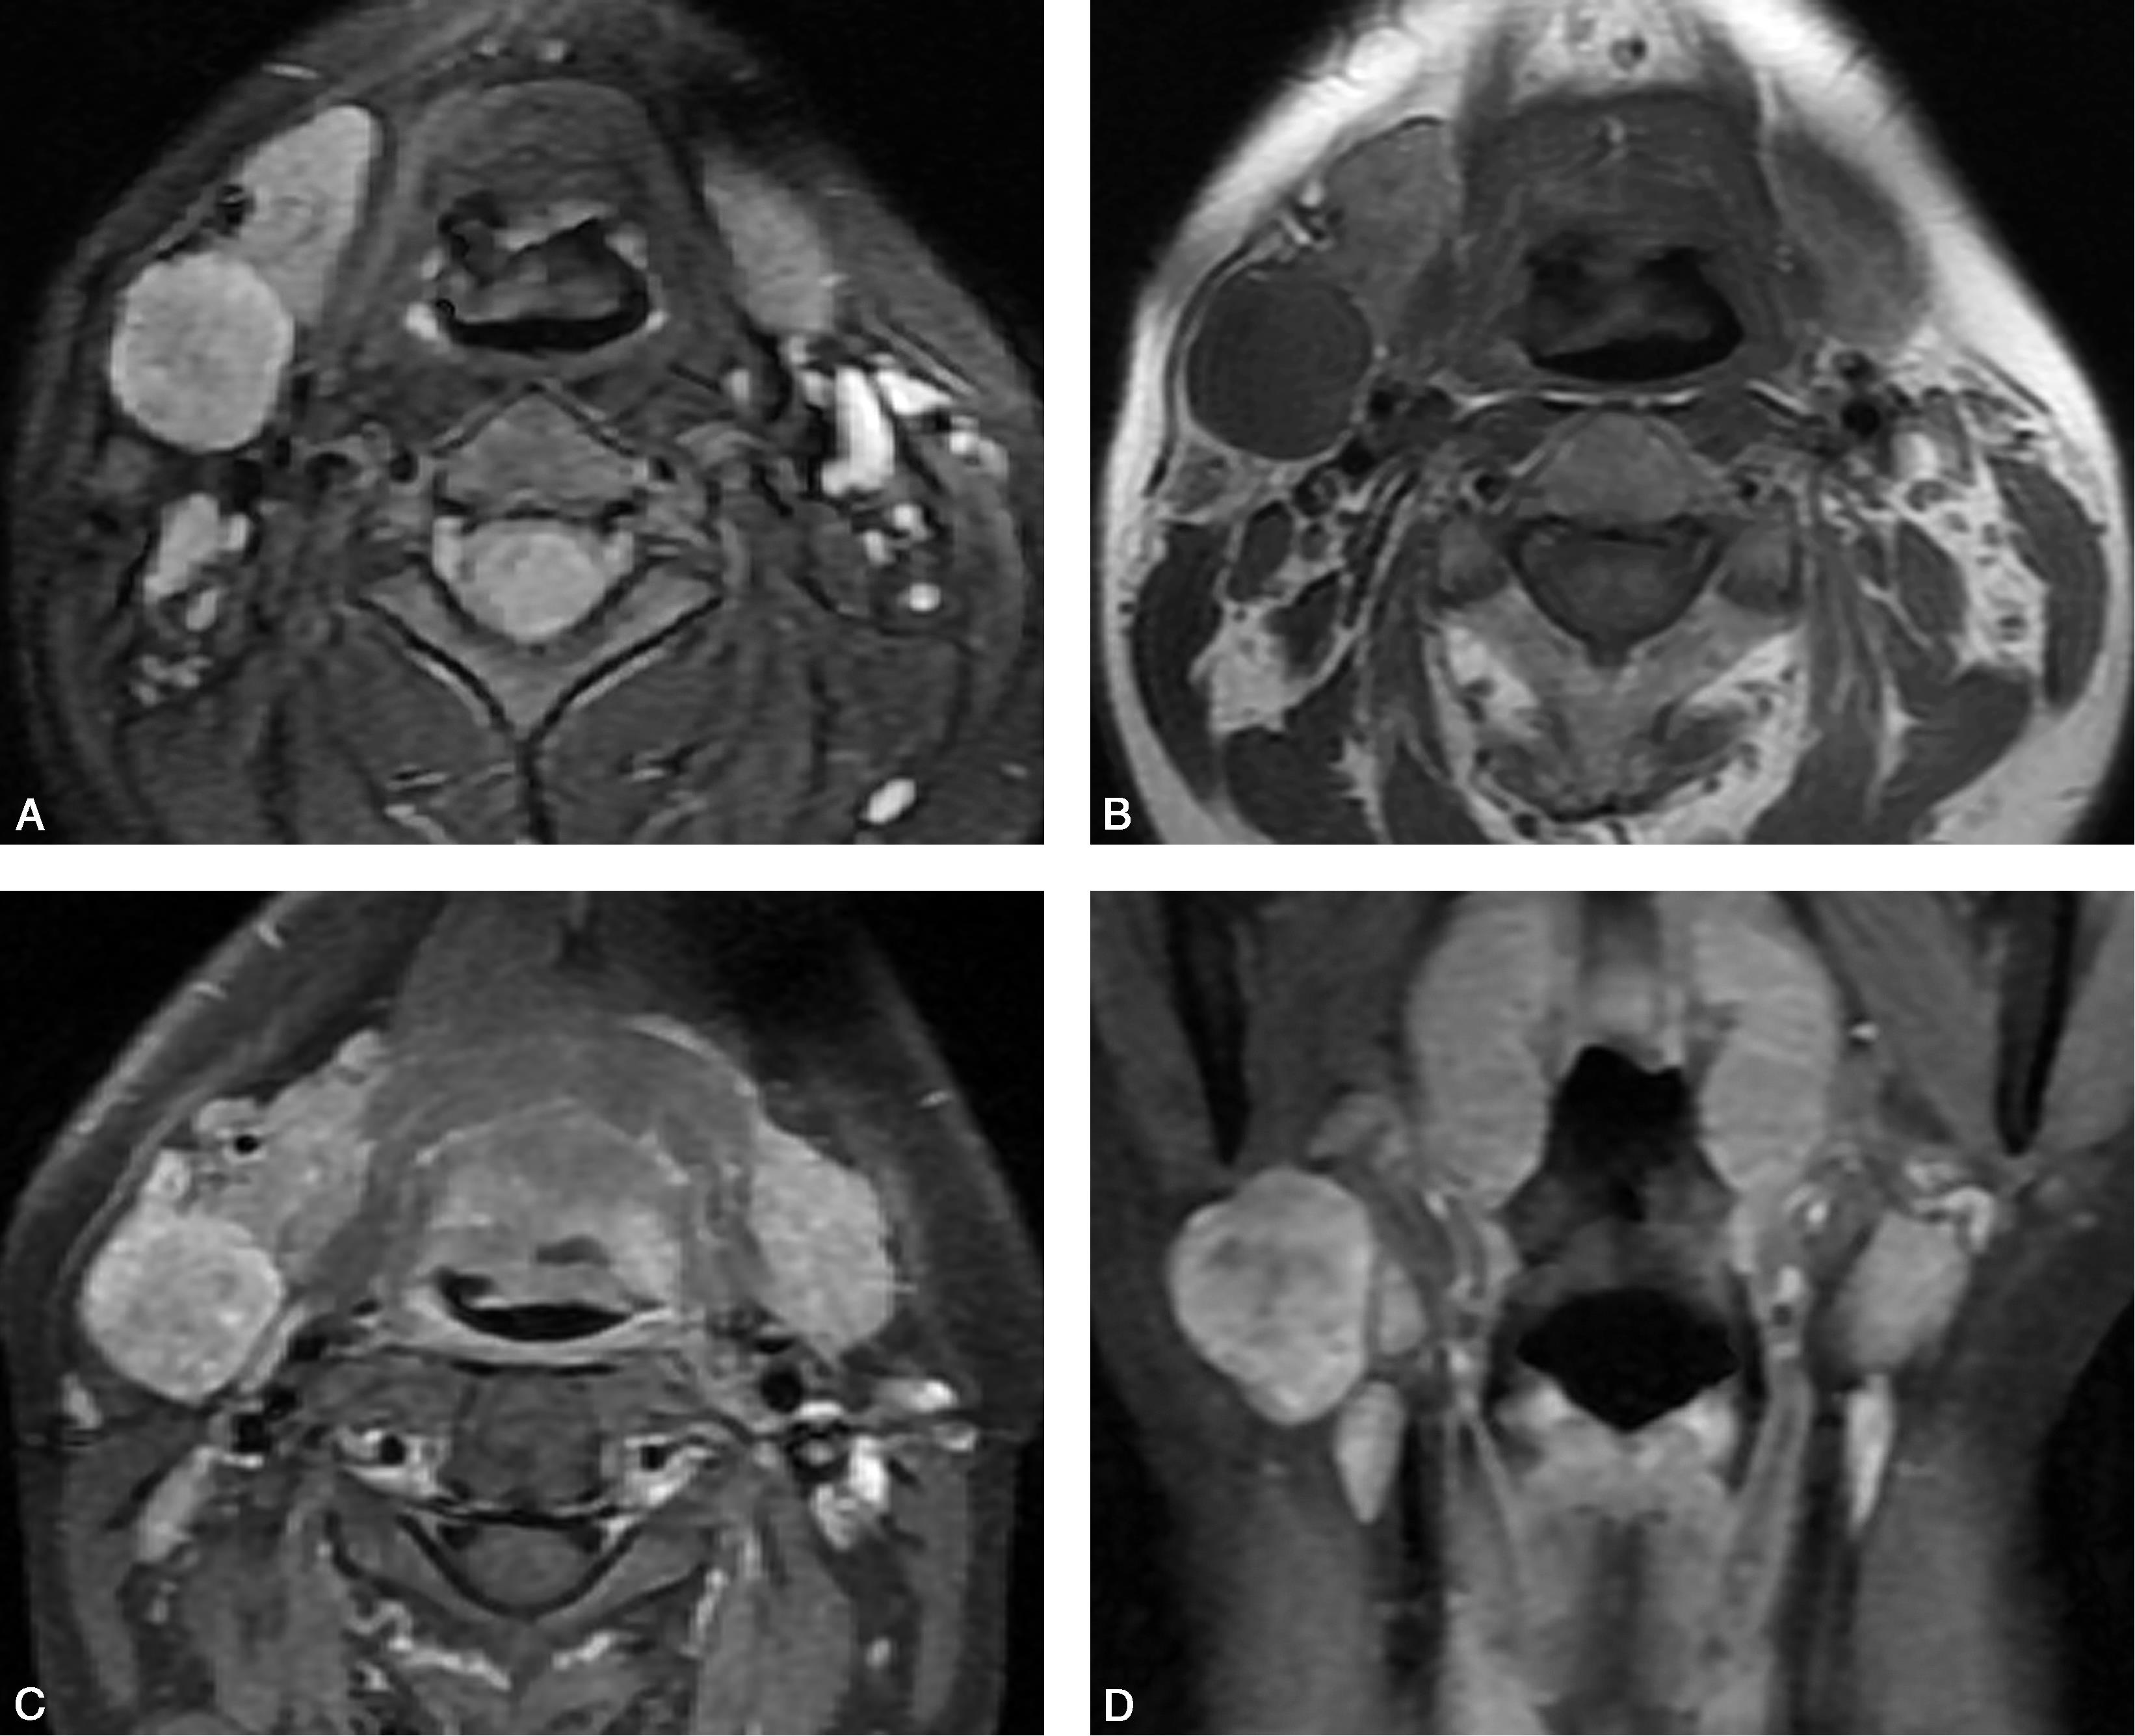

患者,男,29岁,发现颌下肿物8个月(图5-5-1)。

图5-5-1 脂肪瘤1

CT轴位增强(图A、图B)示左侧颌下类椭圆形肿块影,境界清晰,密度均匀,呈低密度,未见明显强化。